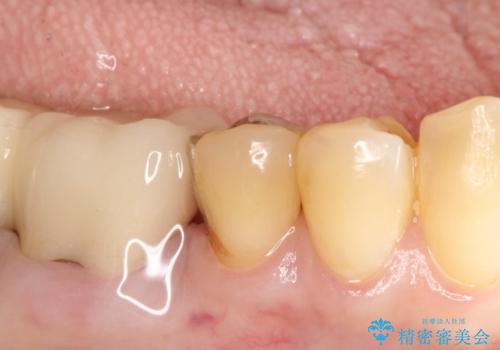

【PGAインレー】深い位置の二次カリエス

- 定期検診にて虫歯を発見したため、PGAインレーにて治療を行いました。